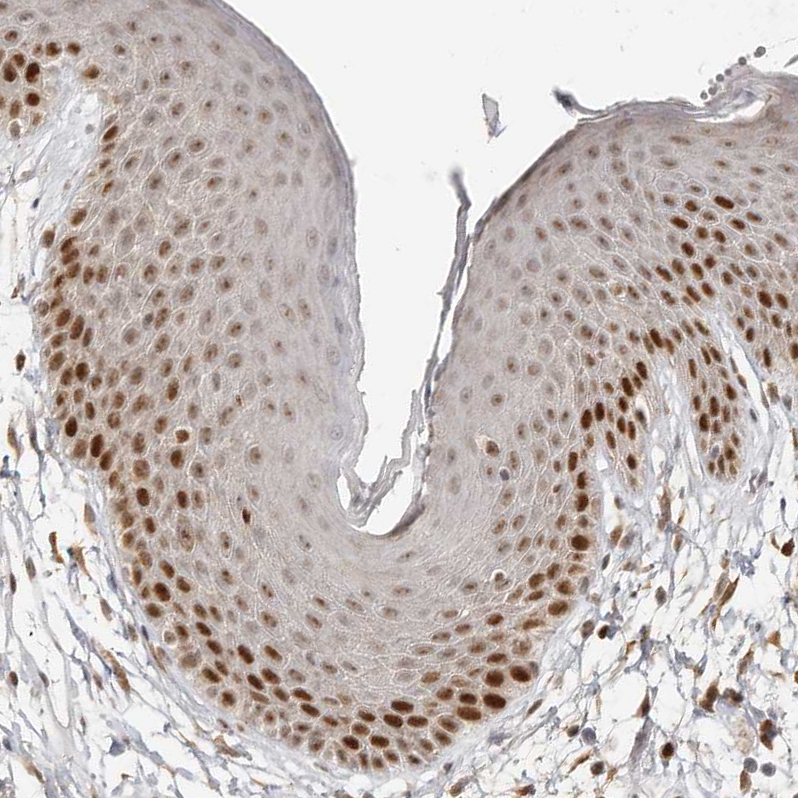

Immunohistochemical staining of human tonsil shows moderate nuclear positivity in germinal center cells.